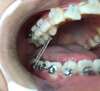

ELASTIQUES

FIM II

FIM III

TRIANGLE

CRISS-CROSS